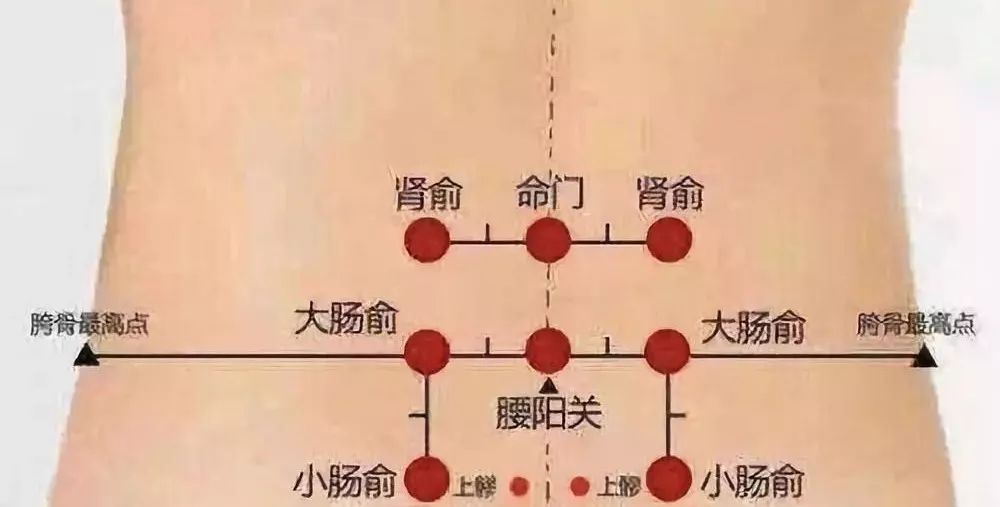

- 腰眼穴为外奇穴,在腰部,第4腰椎棘突下,旁开约3.5寸的凹陷中.

- 肾俞穴在背部腰眼处,即第二腰椎棘突往上两椎体,旁开1.5寸位置.

- 腰眼:第四腰椎棘突下旁开3至4寸

- 肾俞穴(两边腰眼)